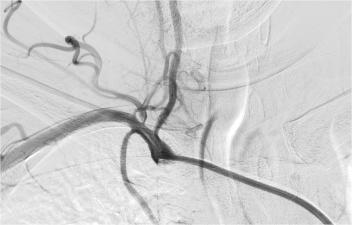

入院查DSA提示右侧椎动脉开口处重度狭窄

胡先生入院后,脑病科随即为他进行中医特色治疗,并行脑血管造影,提示右侧椎动脉重度狭窄、左侧大脑前动脉闭塞,与其沟通后行右侧椎动脉重度狭窄支架植入术,术后恢复良好,配合中医特色治疗5天后,胡先生就出院了,出院时未出现左侧肢体无力,左侧肢体灵活,无明显头晕、眼花,左侧面部麻木症状消失,无明显指端冰凉,入院时存在的症状基本消失,达到基本痊愈的标准。